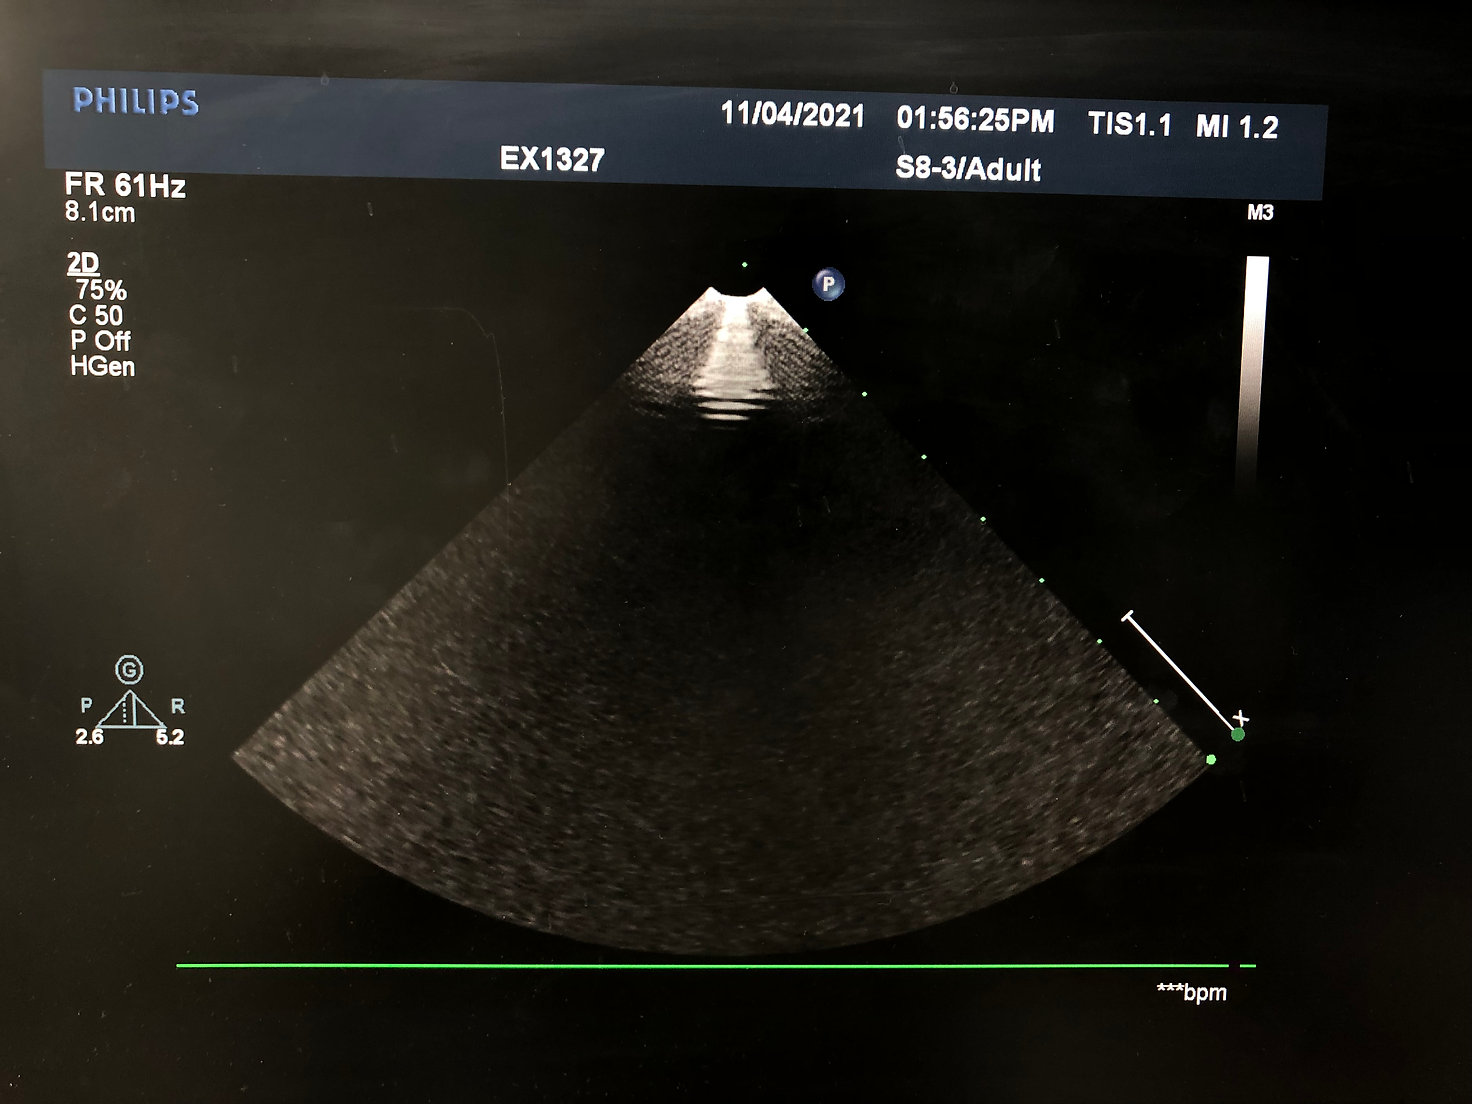

- Transducteur à réseau sectoriel Philips S8-3

- Bande passante : 8-3 MHz

- Champ de vision : 90°

- Applications : applications cardiaques adultes, cardiaques pédiatriques, cardiaques fœtales, abdominales pédiatriques et céphaliques néonatales

- Compatibilité : échographes Philips iE33, HD15, HD11XE et HD11